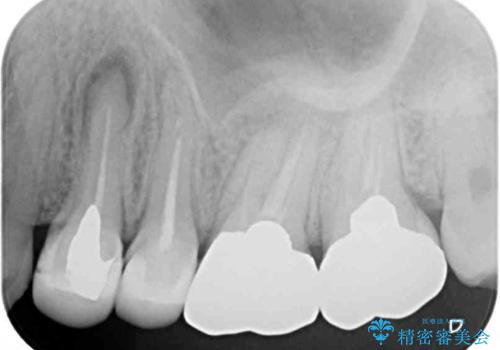

- 笑ったときに見てしまう上顎奥歯の銀歯を気にして来院された患者様です。

折角セラミッククラウンを装着するので、根管治療を行った後に補綴治療を行うこととしました。

他にも目立つ銀歯がありましたが、最も気にしている2本を優先して行うこととしました。